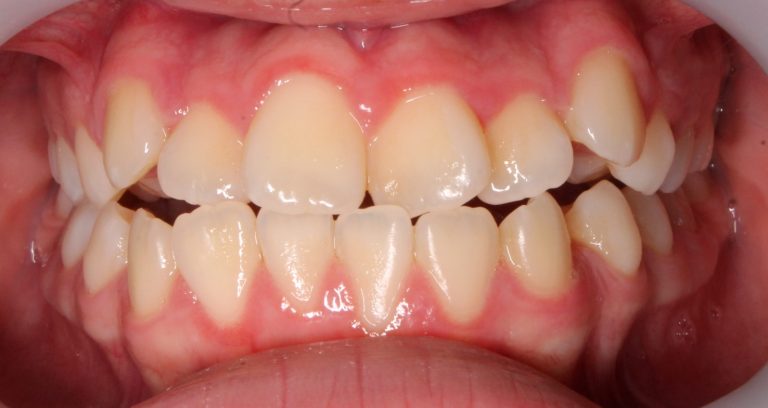

Classe III, articulé postérieur, articulé antérieur, occlusion bout-à-bout, béance, arcades asymétriques, déviation de la ligne médiane mandibulaire, chevauchement, rotations, espacement

État initial